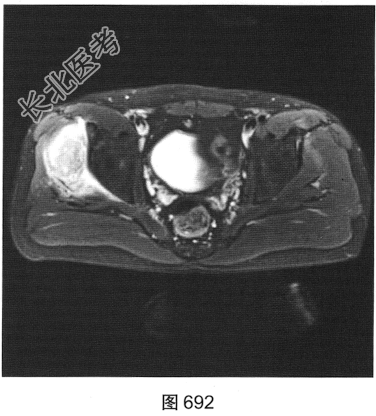

- 多项选择题2.[提示]患者行MRI平扫及增强扫描,见图692~图697。患者MRI平扫及增强扫描图像有哪些阳性表现( )

A、肿块边界不清,信号不均匀

B、肿块周围水肿明显

C、增强扫描肿块呈均匀强化

D、肿块边界清楚,信号均匀

E、增强扫描肿块及周围软组织呈明显不均匀强化

F、与邻近肌肉相比,T1WI呈等信号;T2压脂序列呈明显高信号